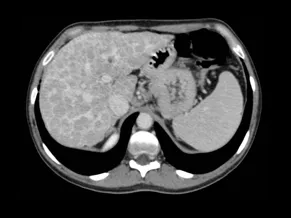

- The cirrhotic liver: morphology and imaging features

- The LI-RADS classification

- Focal lesions in the cirrhotic liver

- Interactive case-based learning — explore real-life examples of focal lesions in the cirrhotic liver and mimickers of cirrhosis